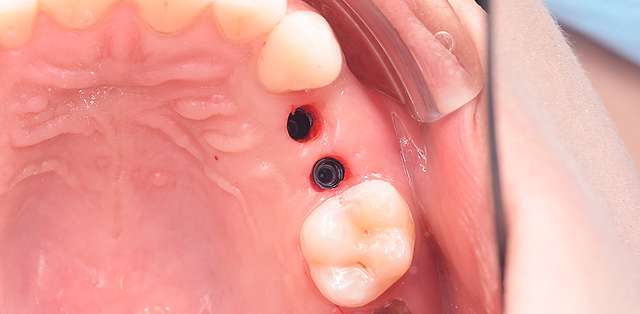

Guided surgery, for one, facilitates an ideal pre-planned position, in relation to available bone, and even more important, in relation to the future implant supported crown. Guided surgery translates into increased precision, which means safer surgeries, reduced surgery time, and reduced trauma. Also the focus of these types of treatments is shifted towards tissue reconstruction, which on the long run, has a far greater impact esthetically and biologically. Tissue stability means implant longevity. This case is a relevant example for this type of approach towards implant dentistry.